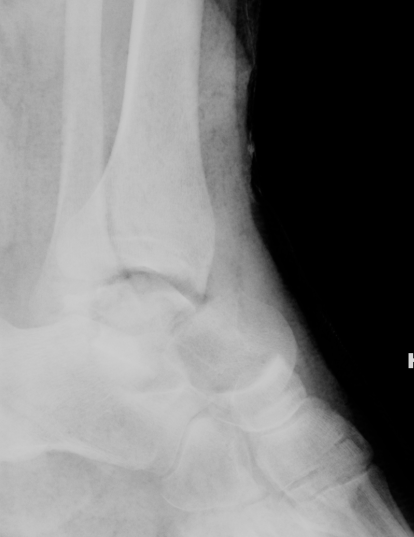

Xrays

| AP | Lateral | Canale View |

|---|---|---|

| Entry point of the screws |

Evaluate neck reduction

|

Evaluates the neck reduction |

Lateral off articular surface Medial through articular cartilage |

Depth of screws |

Beam angled 75o to foot Foot 15o pronated |